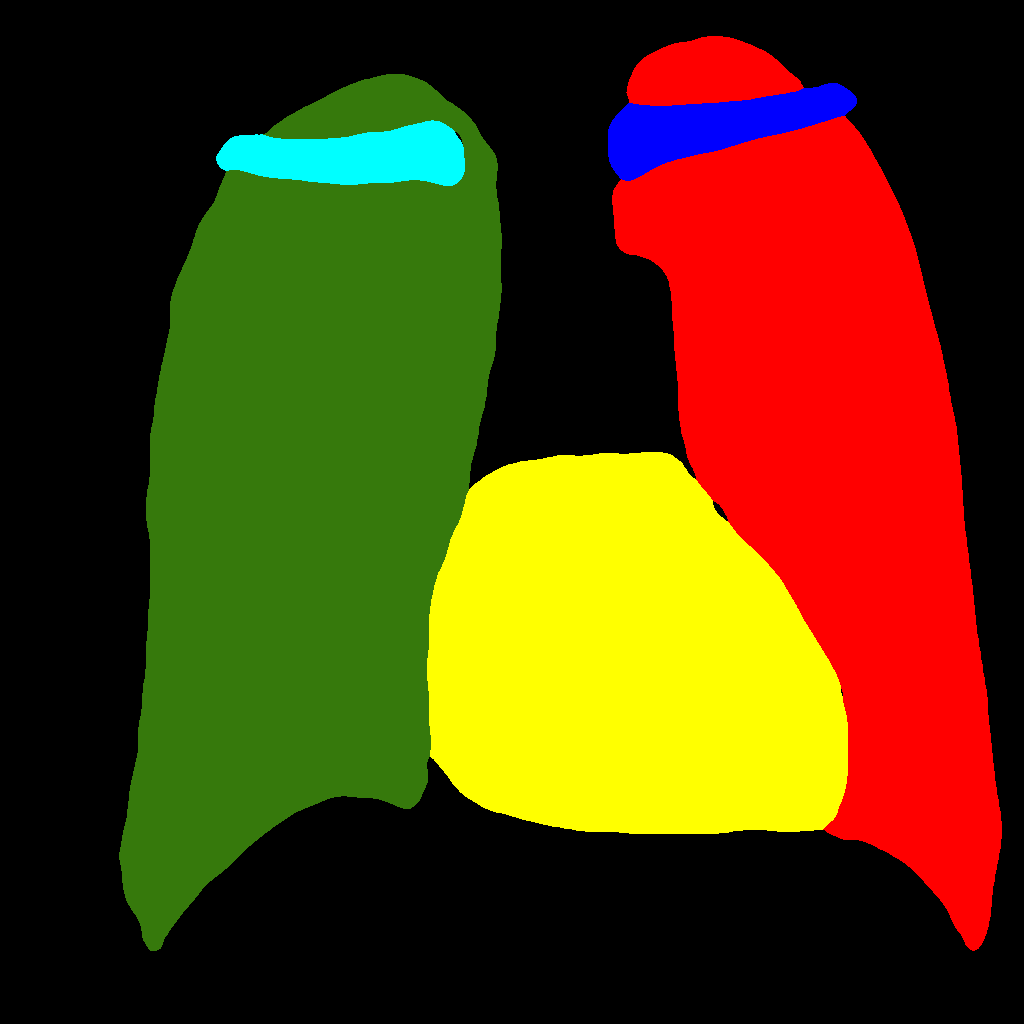

It consists in further subdividing the generation procedure, with a first phase consisting in generating the position and type of the objects that will be generated later, regardless of their shape or appearance. This is obtained by generating label–maps that contain “dots” in correspondence with different anatomical parts (lungs, heart, clavicles). The dots can be considered as “seeds”, from which, through the subsequent steps, the complete label–maps are realized (second phase). Finally, in the last step, chest X–ray images are generated from the label–maps. The exact procedure is described in the following. Initially, label–maps containing “dots”, with a specific value for each anatomic part, are created. The position of the “dot” center is given by the centroid of each labeled anatomic part. The label–maps generated in this phase have a low resolution (), as a high level of detail is not necessary, being the exact object shapes not defined — but only their centroid positions. It should be observed that this also allows to significantly reduce the computational burden of this stage and speedup the computation. The generated label–maps must be subsequently resized to the original image resolution — required in the following stages of generation (a nearest neighbour interpolation has been used to maintain the original label codes) — and translated into labels, which will be finally translated into images, using Pix2PixHD (see Figure 3).

Figure 5 and Figure 6 display some examples — randomly chosen from all the generated images — of the label–maps and the corresponding chest X–ray images generated with the three methods described in Section 3, using the FULL_DATASET and the TINY_DATASET, respectively. We can observe that, with the single and two–stage methods, the images tend to be more similar to those belonging to the training set. For example, in most of the generated images there are white rectangles, which resemble those present in the training images, used to cover the names of both the patient and the hospital. Instead, the three–stage method does not produce such artifacts, suggesting that it is less prone to overfitting.